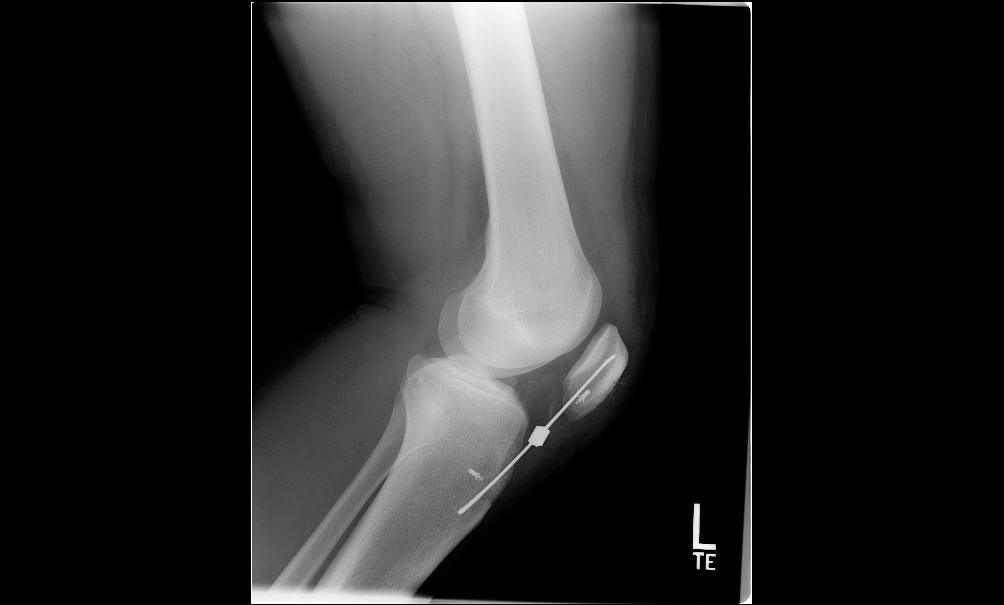

• Difficulty or inability to straighten the leg.

• A visible gap or indentation below the kneecap.

Surgery is often required for complete ruptures to reattach the tendon to the kneecap and restore function:

• Tendon Repair Surgery: Suturing the torn tendon to the kneecap using anchors or stitches.